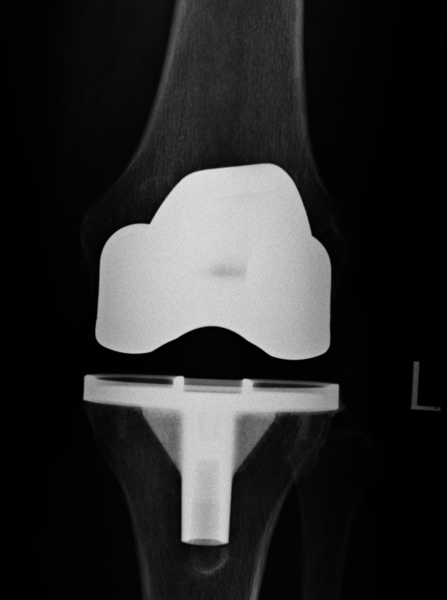

Endoprothetik:

In fortgeschrittenen Fällen, wenn ein großflächiger, schmerzhafter Gelenkverschleiß vorliegt und sämtliche oben genannten Therapieoptionen nicht mehr sinnvoll sind, dann ist - bei entsprechenden Beschwerden - die Therapie der Wahl der Gelenkersatz. Hierbei wird das verschlissene Gelenkareal durch eine künstliche Metalloberfläche ersetzt und zwischen diese Metallpaarung wird als Puffer und zur Verbesserung des Reibungsverhaltens eine Kunsstoffplatte (Polyethylen) eingebracht.